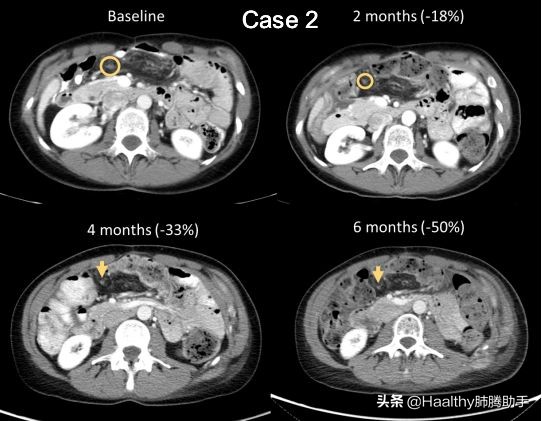

案例2是一名48岁的白人女性。2012年确诊为转移性胆管癌,随后进行化疗。2016年检测到LMNA-NTRK1融合,用拉罗替尼治疗14个月,肿瘤缩小达30%。

后入组TRIDENT-1临床试验,以40 mg QD开始使用Repotrectinib(耐受性良好,第4周期将剂量提升至160 mg QD)。

经研究人员评估,治疗4个月后,肿瘤消退了33%;治疗6个月后,肿瘤消退了50%,但发现新的病灶。

(图7)